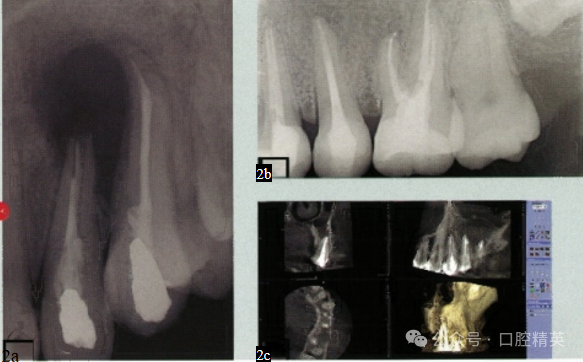

2、如何通过影像学检查确定根管治疗失败?

图:2a X 线片上存在根尖周低 密度影,这是根管感染的典型 表现。

图:2b 根尖周低密度影像模糊 不清,二维X线片不能准确反 映根尖周病变的范围。

图:2c 三维影像学检查(CBCT)可以确定根尖周病变的范围。